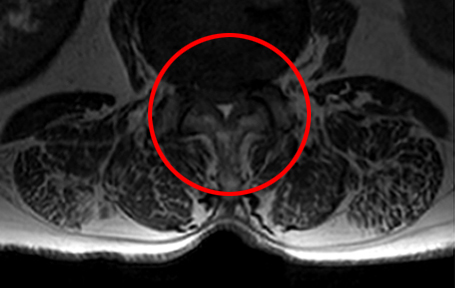

• 모커리한방병원 MRI로 본 중증 척추관협착증 이미지

중증 척추관협착증 상태

척추관협착증은 척추 뼈와 인대, 후관절, 디스크 등이 전체적으로 모두 퇴행되어 척추관이 좁아지고 신경압박이 발생하는 질환입니다.